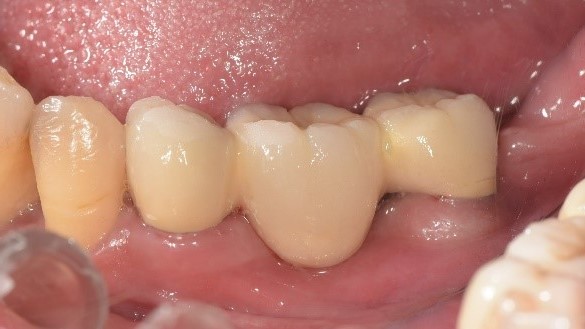

治療前